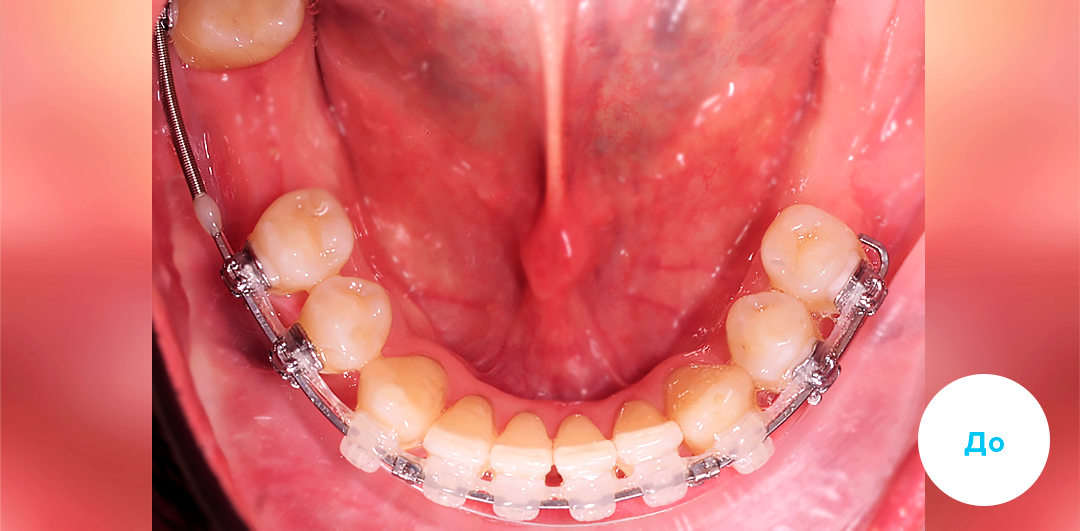

До

После

ЛЕЧЕНИЕ ДЕФИЦИТА МЕСТА НА ЧАСТИЧНОЙ БРЕКЕТ-СИСТЕМЕ У ДЕТЕЙ

Смотреть кейс